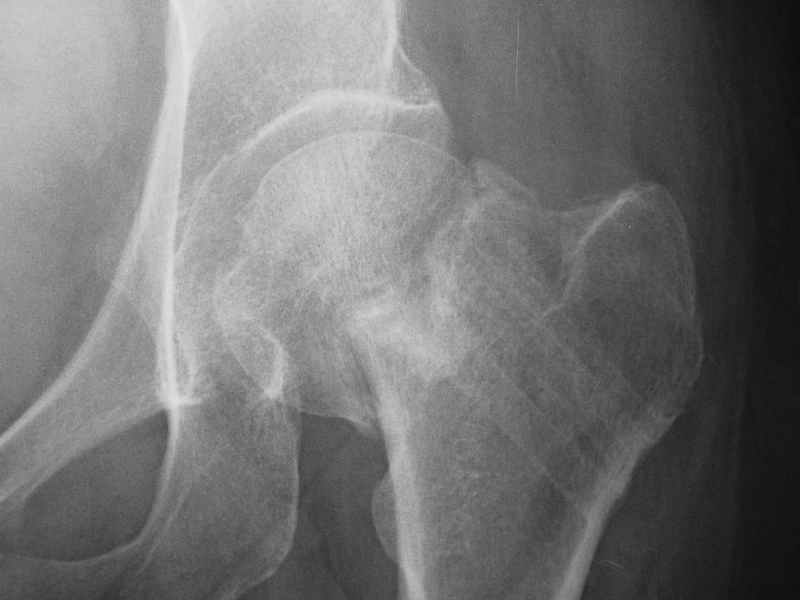

Re: Нелеченный перелом шейки бедра / Neglected fem

dhs will not correct improper biomechanical environment and may further compromise vascular

integrity consider establish vascular status via mri

and if viable follow with proximal valgus osteotomy

case provided s/p failed fixation